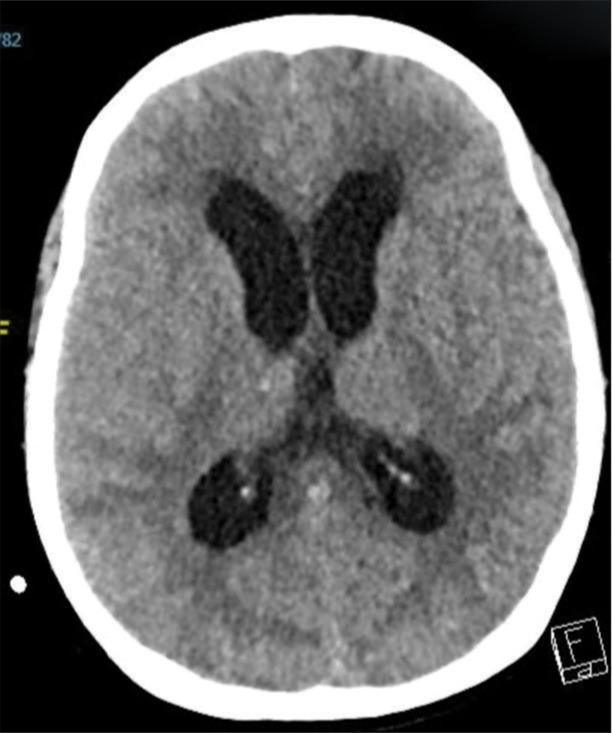

CASE DESCRIPTION

The case describes a 49-year-old Filipino woman with a history of hypertension who presented with symptoms strongly suggesting KBS following subarachnoid hemorrhage, including behaviors such as hyperorality, hypermobility, placidity, hypermetamorphosis, and hypersexuality along with memory disturbance. She was managed as a case of brief psychotic disorder initially with olanzapine, then on the second presentation as a case of delirium with risperidone.

该病例描述了一名49岁有高血压病史的菲律宾女性,蛛网膜下腔出血后出现强烈提示KBS的症状,包括口欲亢进、多动、平静、变换症和性欲亢进等行为以及记忆障碍。她最初被当作短暂性精神病性障碍病例用奥氮平治疗,第二次就诊时被当作谵妄病例用利培酮治疗。